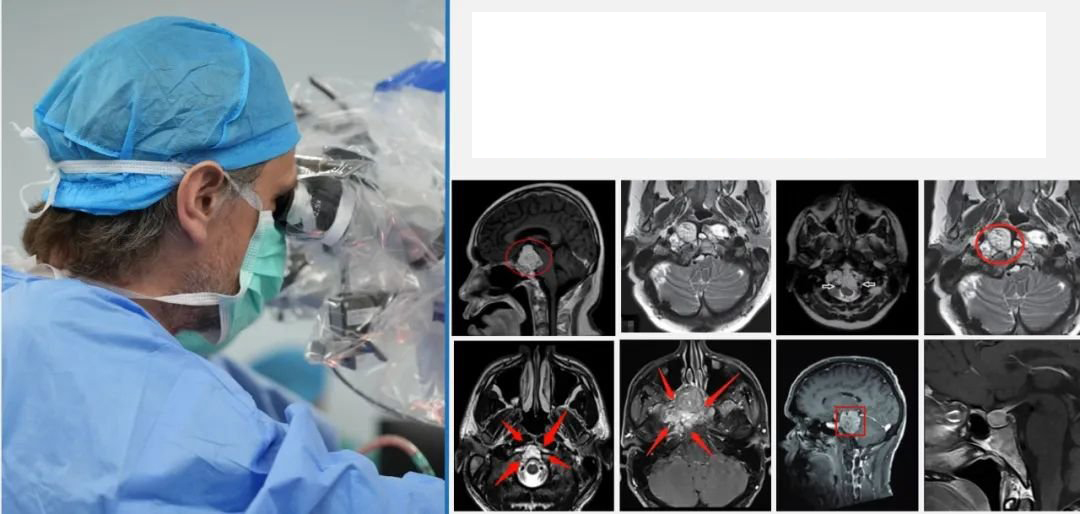

神经外科显微镜+内镜”双镜联合“手术教授

复杂颅底手术的国际高手

INC法国福洛里希教授对于开颅手术及神经内镜各个手术入路都运用得炉火纯青,并了神经内镜“筷子技法”,娴熟得运用到颅底肿瘤的手术之中。针对复杂颅底肿瘤,福洛里希教授会根据具体病情,内镜或是开颅、还是选择神经内镜+显微镜“双镜联合”,从而达到肿瘤较大水平的顺利切除,确定患者的术后生活质量,带来更好的预后。

48岁男性较大脊索瘤复发,“双镜联合”成功手术

53岁男性高难度岩斜区脑膜瘤